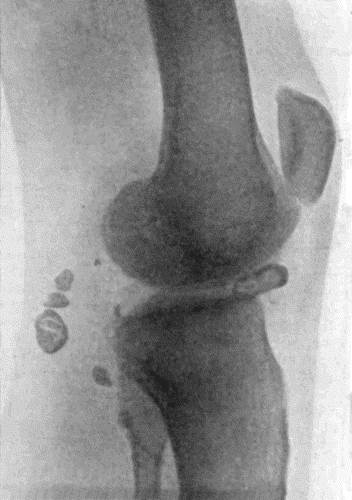

138.Radiogram of Right Knee showing Multiple Exostoses 482

139.Multiple Exostoses of Limbs 483